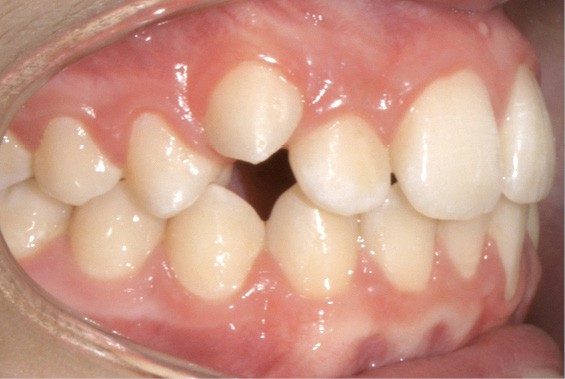

Examen endo-buccal (fig. 2a-e)

Au niveau des relations occlusales, on observe une Classe I molaire associée à une Classe II canine de 2 mm à droite ainsi qu’une Classe II molaire de 1 mm et une Classe II canine de 3 mm à gauche. Le surplomb est normal.